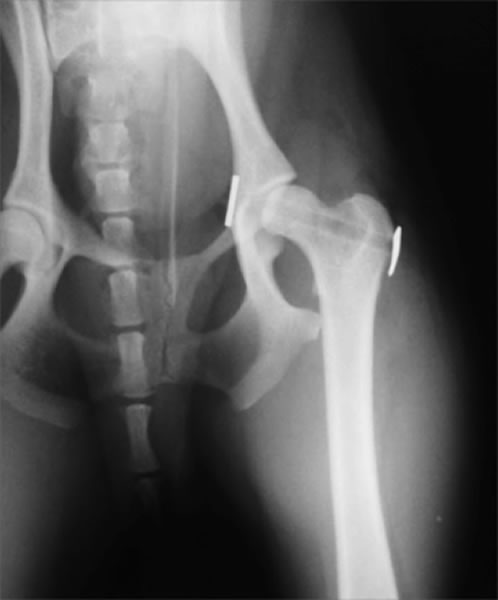

THR(Total Hip Replacement)/ 股関節全置換術

Micro THR(Micro Total Hip Replacement)/ 小型犬・猫用股関節全置換術

全股関節置換術は股関節形成不全やその他の股関節の異常(レッグペルテス、骨頭骨折等)に対して行われる根治的治療法で、機能の回復に関しては現在のところ最もすぐれた治療法です。機能しない、あるいは痛みを持つ股関節をチタンの人工関節に取り替える方法です。6カ月齢からあらゆる年齢で可能な手術です。